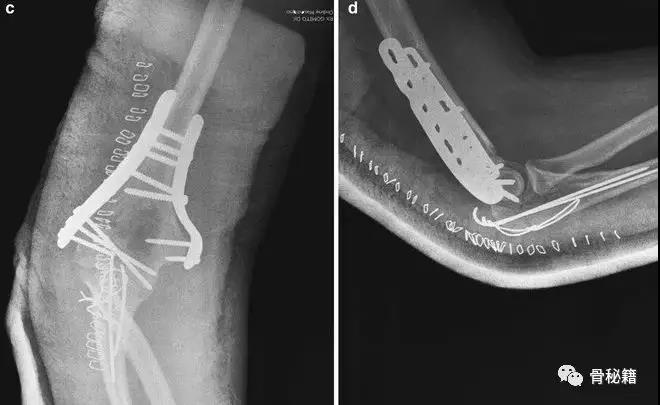

适当的固定技术原则

1、最大限度地固定远端碎片2、确保远端节段的所有固定有助于提高髁间水平的稳定性3、不建议使用三分之一管型板,因为它们太弱的并易于断裂,尤其是在粉碎干骺端

4、钢板长度也很重要:板应在近端以不同水平,以避免在肱骨干骨中形成应力集中

5、解剖锁定钢板板通过卓越的生物力学特性提供更好的临床疗效

6、良好的固定需要两个板,平行or垂直?在肱骨远端骨折中,一块钢板通常不足以保证良好的稳定性,而在其他骨折(例如,胫骨近端和股骨远端)中,LCP的引入消除了对双柱固定的需要。应谨慎使用单侧钢板板,仅在单柱损伤的情况下可以应用。

7、钢板如何搭配?迄今为止,通常使用前两种钢板的固定。AO推荐在治疗中应用垂直钢板。然而,这种方法受到了广泛的批评 - 主要是因为通过后外侧板难以获得足够的螺钉数量和前后方向的长度的螺钉固定。与垂直钢板相比,平行板配置似乎提供了更好的生物力学性能。实在不行的时候再用三钢板技术

固定的八个细节:1、每个螺钉都应该经过钢板固定2、每个螺钉固定骨折块的螺钉,在他的对侧应该也有一个钢板的把持3、在远端一定要打满螺钉4、每个螺钉要尽可能的长5、每个螺钉需要尽量的对关节面的骨块进行固定6、螺钉应通过交叉锁定在一起,从而形成角稳定结构并将内外侧柱连接在一起7、钢板需要再髁间完成加压8、所使用的板必须足够坚固并且足够坚硬以抵抗在髁上水平处的断裂或弯曲。